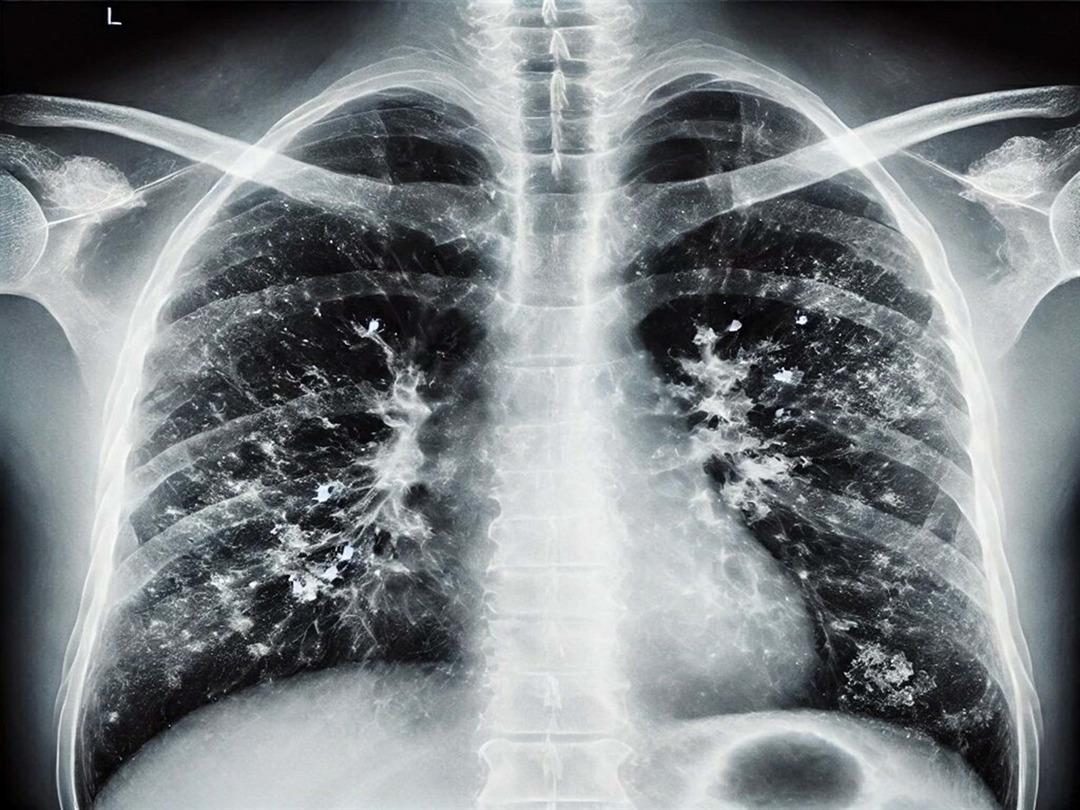

Özellikle 65 yaş üstü vatandaşlara yönelik uyarılarda bulunan Prof. Dr. Şener, "Bu grupta RSV dediğimiz viral enfeksiyon önem taşıyor. RSV, akciğerde yaygın enflamatuar tabloya sebep oluyor. Bunun da aşısı var. Cebinizden ücret ödeyerek yaptırabileceğiniz bir aşı. Özellikle 75 yaş üstü bireylerin mutlaka olması gerekiyor. 65 yaş üstünden başlarsak viral enfeksiyonlar ağır seyrediyor. Koronavirüs döneminde bunlara alışkındık; pandemi sonrasında da ağır viral enfeksiyon tablolarıyla karşı karşıya kalmaya başladık. Ciddi solunum yetmezliği, ateş, üşüme ve titreme semptomları; acil servise başvuru ve oksijen desteğine rağmen toparlanamama gibi durumlar görüyoruz. Bu nedenle bu hastalar, bazen normal servise bazen de yoğun bakıma yatmak zorunda kalıyor. Bu hastalar maalesef bazen her türlü tedaviye rağmen akciğerdeki ağır enfeksiyonun yaygınlaşmasıyla ölüme kadar ilerleyebilen klinik tablolara sebep olabiliyorlar" diye konuştu.

Hastalığı ayakta geçirenlere yönelik de değerlendirmelerde bulunan Prof. Dr. Şener, "Hafif geçirseler bile akciğerlerdeki hasar ilerleyen dönemlerde KOAH ve astım gibi tablolara sebep olabiliyor. Sonrasında ömür boyu ilaç kullanmak zorunda kalıyorlar. Bu konu da önemli. Bir diğer tablo ise kalp hastalığı, hipertansiyon ve diyabeti olanlar. Bu kişiler de ağır klinik tablolar geçiriyor. Atlattıktan sonra bakteriyel enfeksiyonlar sık görülüyor. Viral enfeksiyonu hastanede atlattıktan sonra geçmeyen öksürük nöbetleri ve balgam yaşanıyor. Bundan sonra da zatürre dediğimiz tablolar oluşuyor. Bu durumda kesinlikle antibiyotik alınması lazım. 65 yaş üstü gruba mesaj gitmesi gerekirse; hafif bir gribal enfeksiyon geçirdikten sonra öksürük ve balgam devam ediyorsa, uzman doktora veya aile hekimine mutlaka görünmek gerekiyor. Belki de zatürre oldunuz ve farkında değilsiniz. Gerekli tetkiklerin yapılması ve antibiyotik başlanması lazım" dedi.